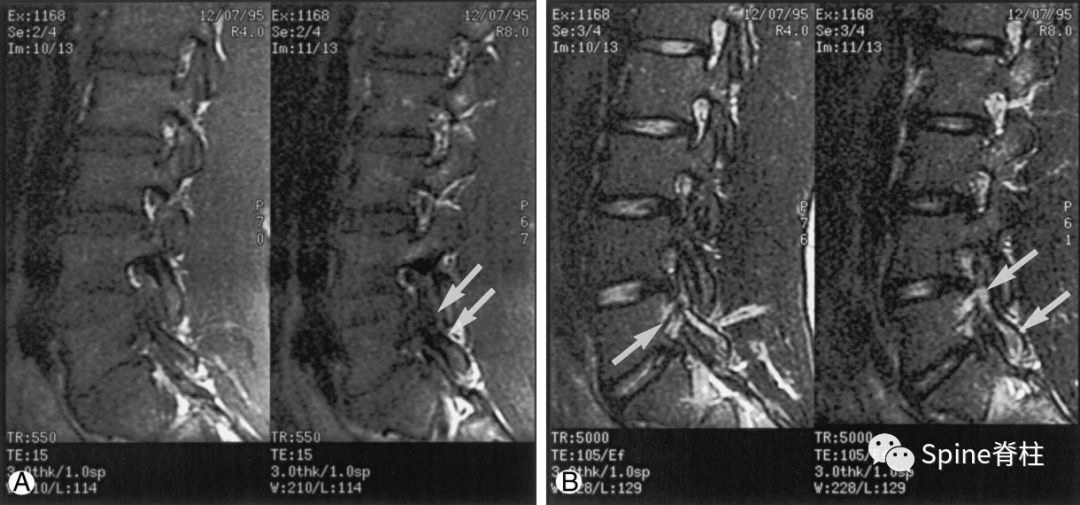

16岁的足球运动员诉右腰部疼痛。A:右侧T1加权像可见腰5峡部和椎弓根呈低信号(箭头);B:右侧T2加权像可见腰5峡部、椎弓根和关节突呈高信号(箭头)。

图:T2水肿信号且峡部皮质不连续断裂

提示L3左侧峡部裂(2级)

17岁的篮球运动员诉腰痛。A:T1像,左侧腰3峡部呈不连续的低信号(箭头);B:T2像,左侧腰3椎弓根和峡部呈高信号(箭头)